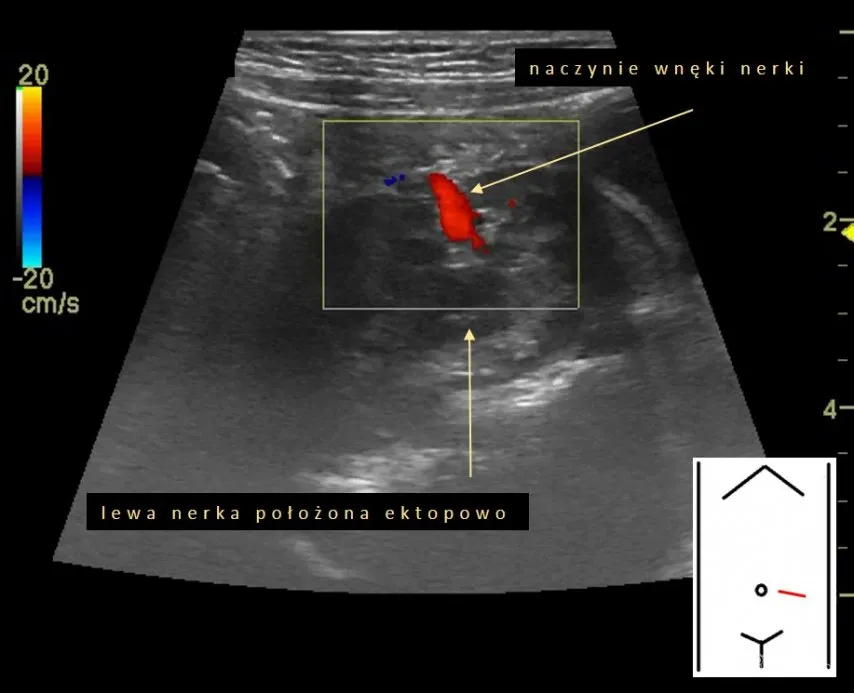

- Wielkość, kształt i położenie nerek: Odchylenia od normy mogą wskazywać na różne schorzenia.

- Zmiany w naczyniach nerkowych: Choć do pełnej oceny naczyń często potrzebne są bardziej zaawansowane techniki, USG może wstępnie wskazać na pewne nieprawidłowości.